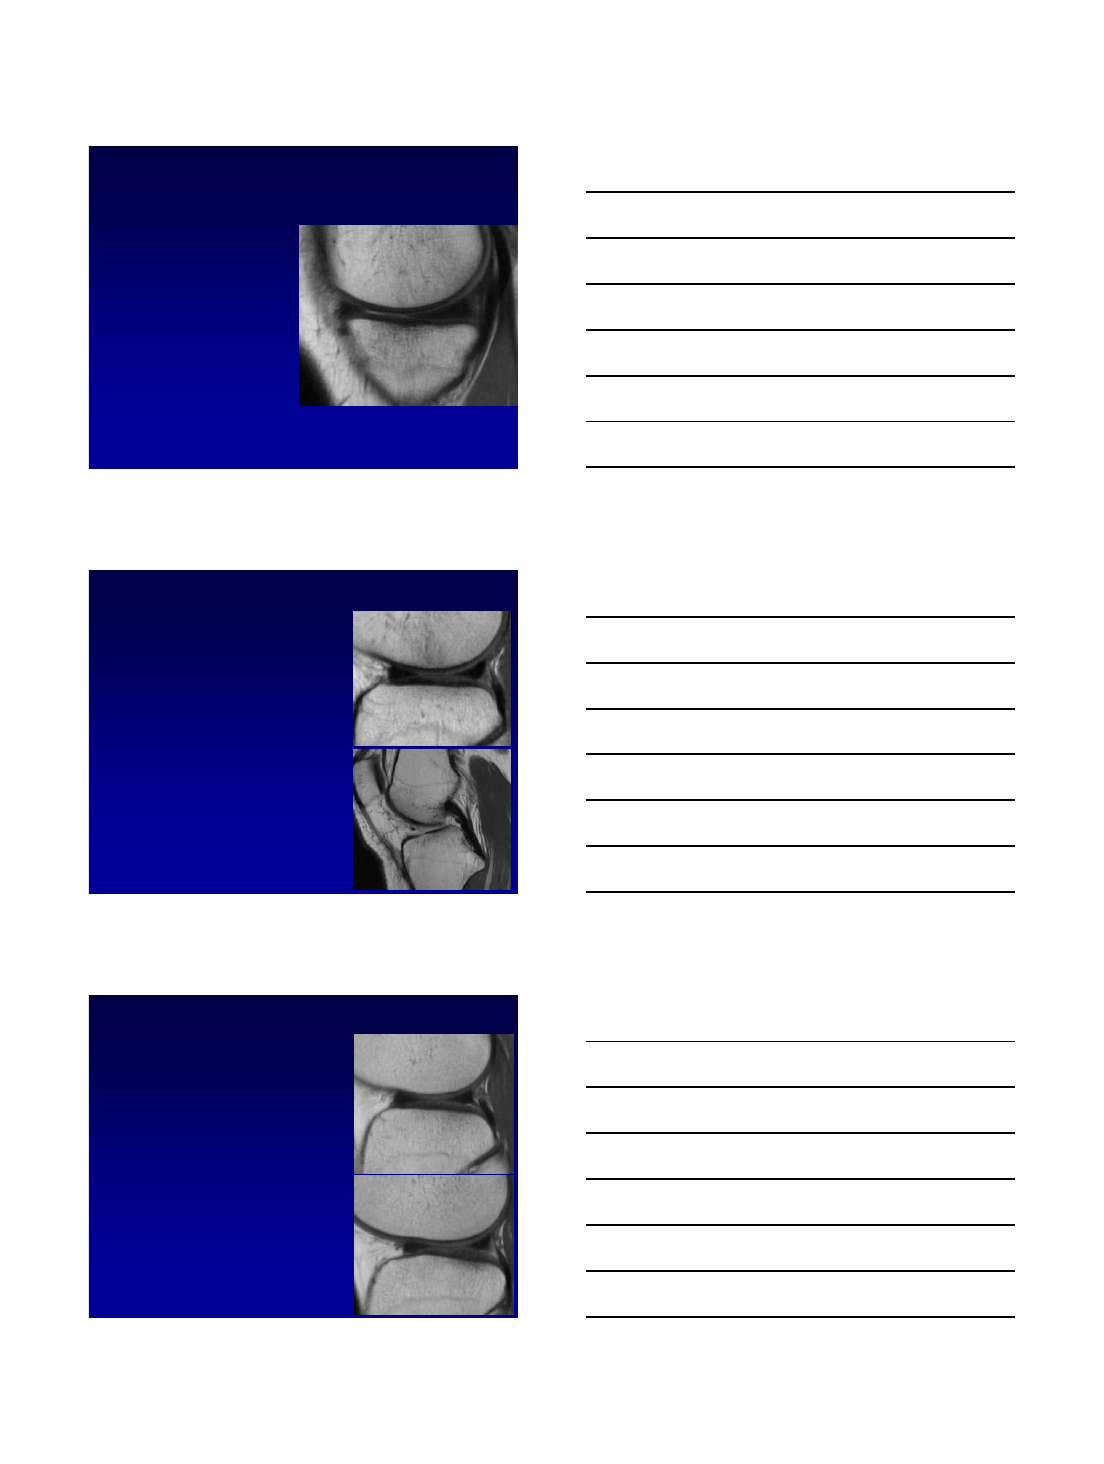

•Semilunar (C–shaped)

–Medial is more C-shaped and larger and lateral more rounded and smaller

•Divided into anterior and posterior horns and body

Medial Meniscus

•Posterior horn is larger than

anterior horn

•Non-mobile –more firmly

attached to the joint capsule

Discoid meniscus

•Watanabe classification: Complete,

Incomplete* and Wrisberg variants

•Non-tapering of apex of meniscus

•Radial diameter > 13 mm

•Increased height >2mm than opp meniscus

•Predisposes to degeneration and tear

•Pain, clicking, mechanical locking